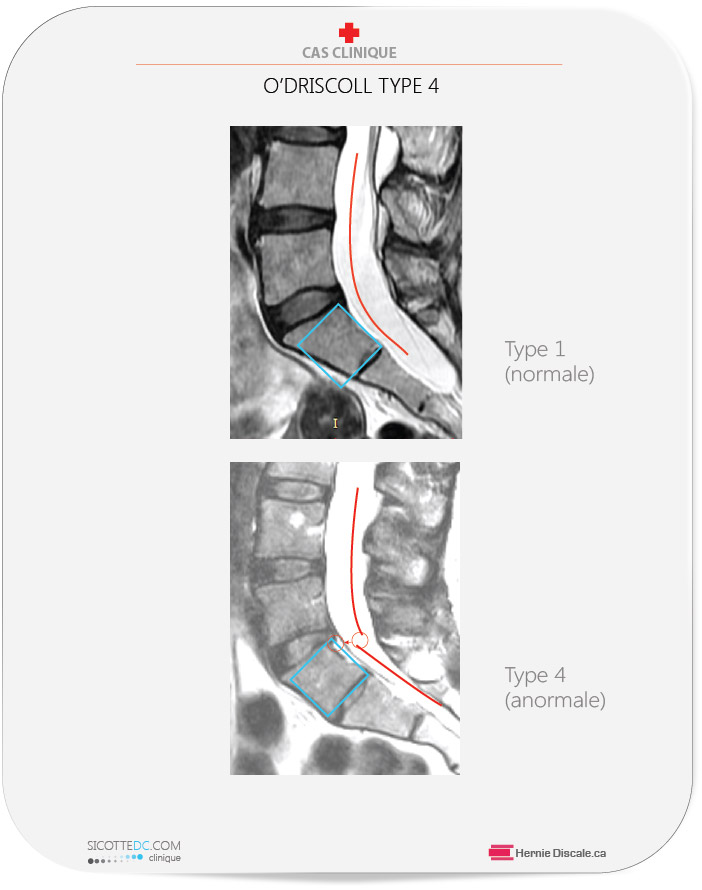

CLASSIFICATION O’DRISCOLL

Type 2: Contient un petit disque transitionnel. Les disques possèdent un diamètre inférieur à la distance antéro-postérieure de la vertèbre sacrée S1. Présent chez les patients qui ne possèdent pas de segment transitionnel.

Type 3: Un disque qui s’étend sur toute la distance antéro-postérieure de la vertèbre S1. Présent chez les patients qui ne possèdent pas de segment transitionnel, mais fréquent chez ceux qui ont l’anomalie du segment transitionnel.

Type 4: Similaire à celle du type trois, mais la vertèbre sacrée est de forme carrée.